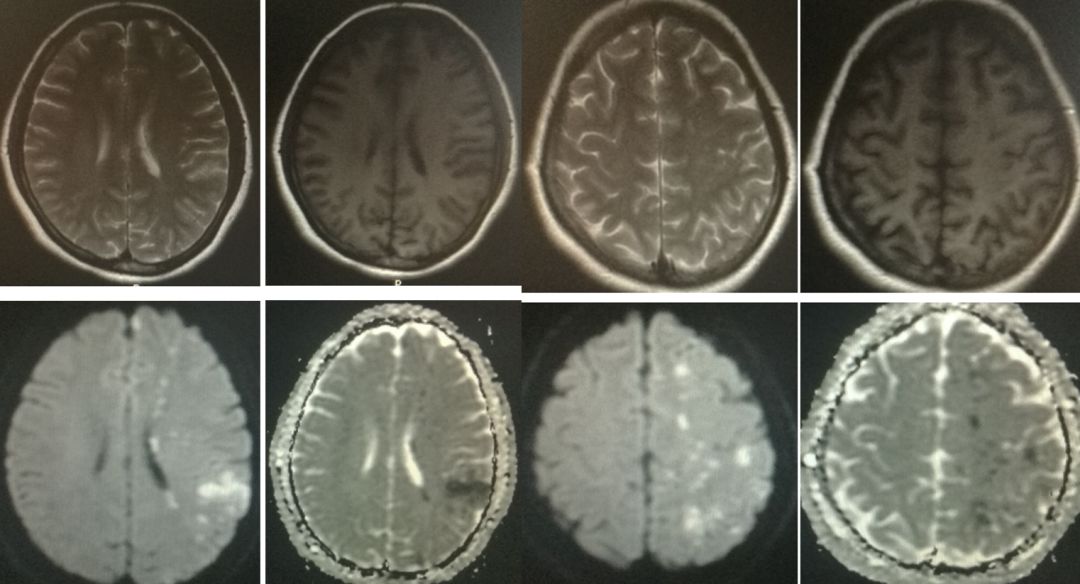

答案:脑梗死,嗜酸性粒细胞增多症。

患者老年女性,双侧多动脉流域脑梗死,老师们都想到了特鲁索综合征,嗜酸性粒细胞增多症等。从形态学上更趋向于嗜酸性粒细胞增多症,特点是都在皮层,病灶连续,类似于缎带。急性多发性脑梗死(AMIMC)被认为提示存在心源性栓塞或全身性凝血功能亢进。AMIMC的发生机制或同时发生的机制尚不清楚。ADC的发现提示AMIMC通常是逐渐发生的,全身性炎症可能与AMIMC的发病机制有关。该患者证实为嗜酸性粒细胞增多症。值得提醒的是,嗜酸性粒细胞增多症有很大一部分是某些疾病症状,如变态反应性疾病、寄生虫感染、皮肤病、结缔组织病以及肿瘤等,还有一部分是特发嗜酸性粒细胞增多综合征。治疗方案也不同,继发性以去除病因为主,原发性可能需要使用激素和干扰素等。

女性,33岁,突发肢体抽搐4小时。

答案:脑梗死,继发性癫痫,心房粘液瘤。

本患者影像与上一例有相似之处,也是多发。区别是本患者是青年卒中,且局限于左侧,梗死分布于大脑前中、前后动脉交界区,呈串珠状,考虑混合型分水岭梗死。青年卒中病因比较繁多,需要进行筛查,下图列出了青年卒中的常见病因: